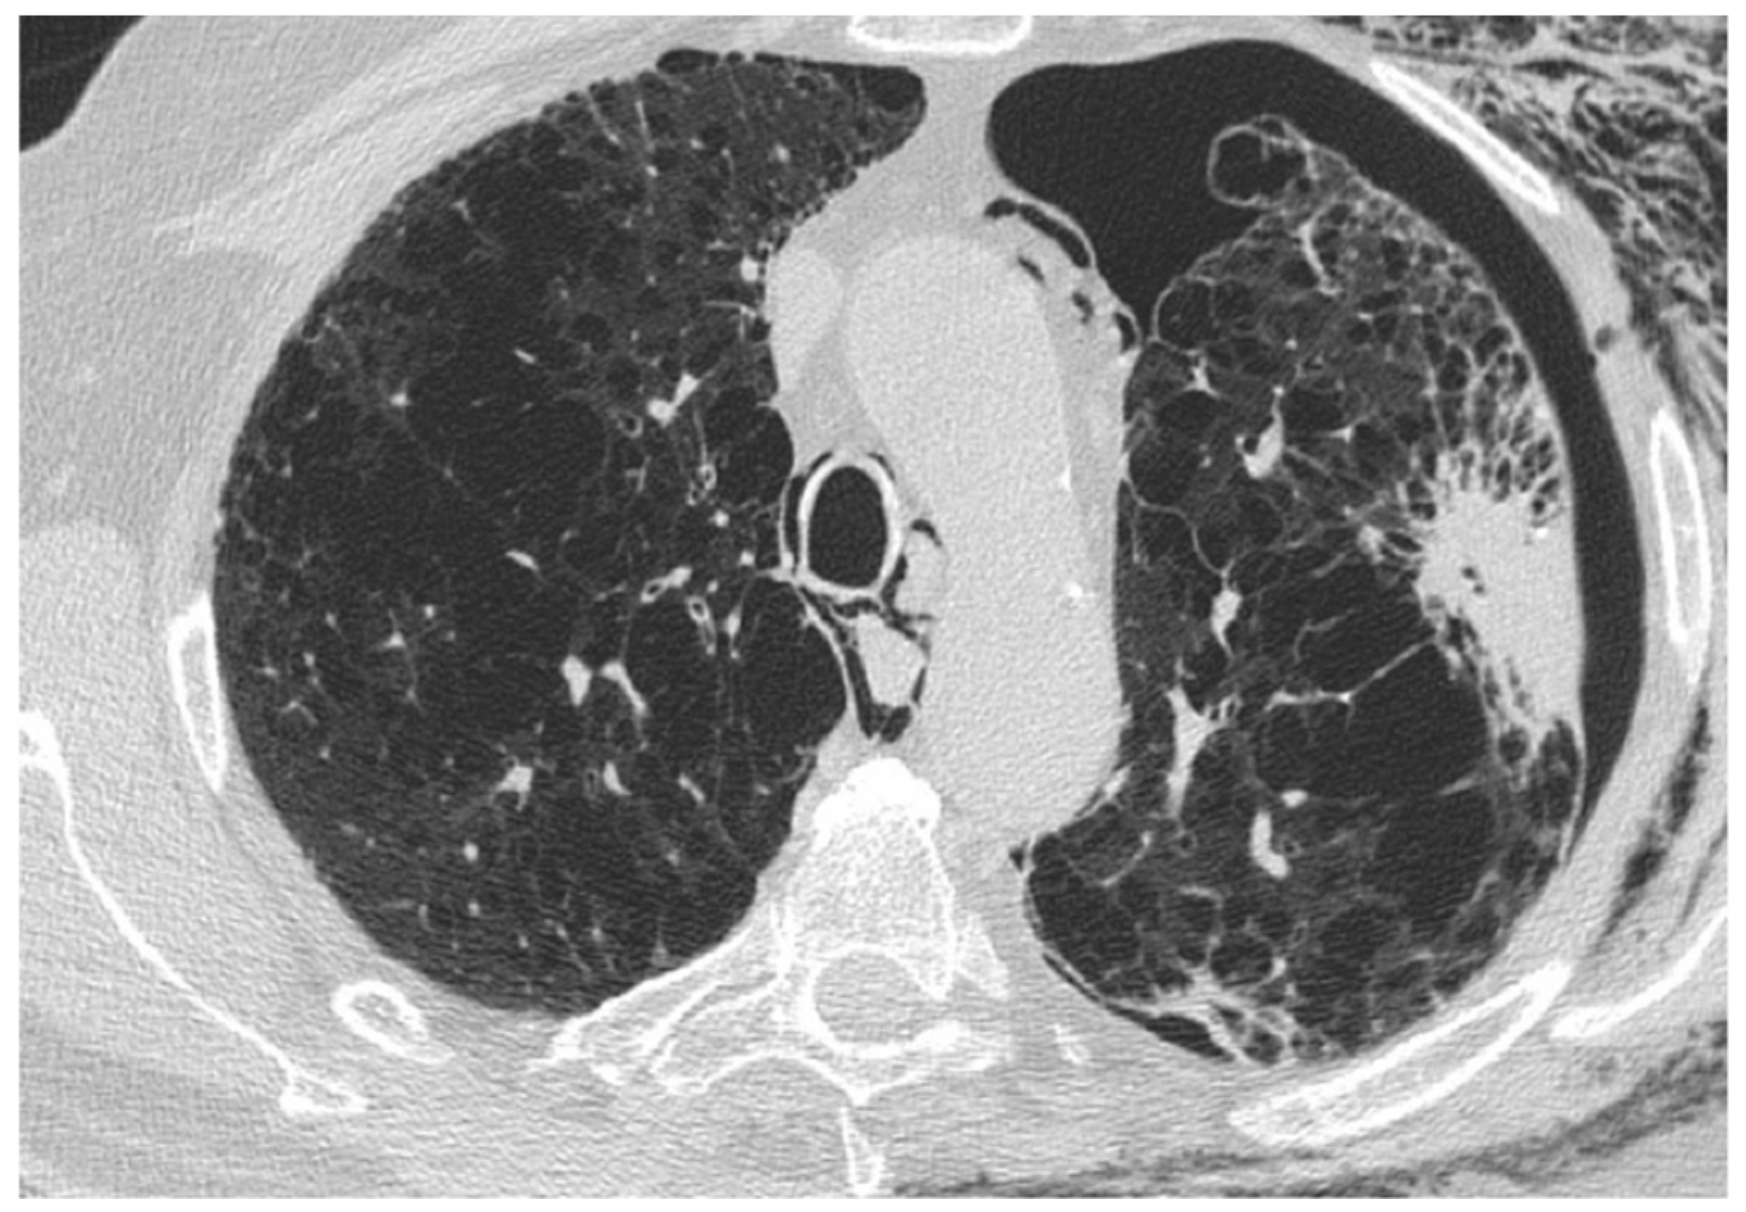

| Acute exacerbation IPF | New bilateral ground glass opacities and/or consolidation on a background of reticular or honeycombing pattern. | ||

- Silva, C.I.S.; Müller, N.L.; Fujimoto, K.; Kato, S.; Ichikado, K.; Taniguchi, H.; Kondoh, Y.; Johkoh, T.; Churg, A. Acute Exacerbation of Chronic Interstitial Pneumonia: High-resolution Computed Tomography and Pathologic Findings. J. Thorac. Imagin. 2007, 22, 221–229. [Google Scholar] [CrossRef] [PubMed]

- Sokai, A.; Tanizawa, K.; Handa, T.; Kubo, T.; Hashimoto, S.; Ikezoe, K.; Nakatsuka, Y.; Aihara, K.; Taguchi, Y.; Muro, S.; et al. Asymmetry in acute exacerbation of idiopathic pulmonary fibrosis. ERS Monogr. 2017, 3, 1–8. [Google Scholar] [CrossRef] [PubMed]